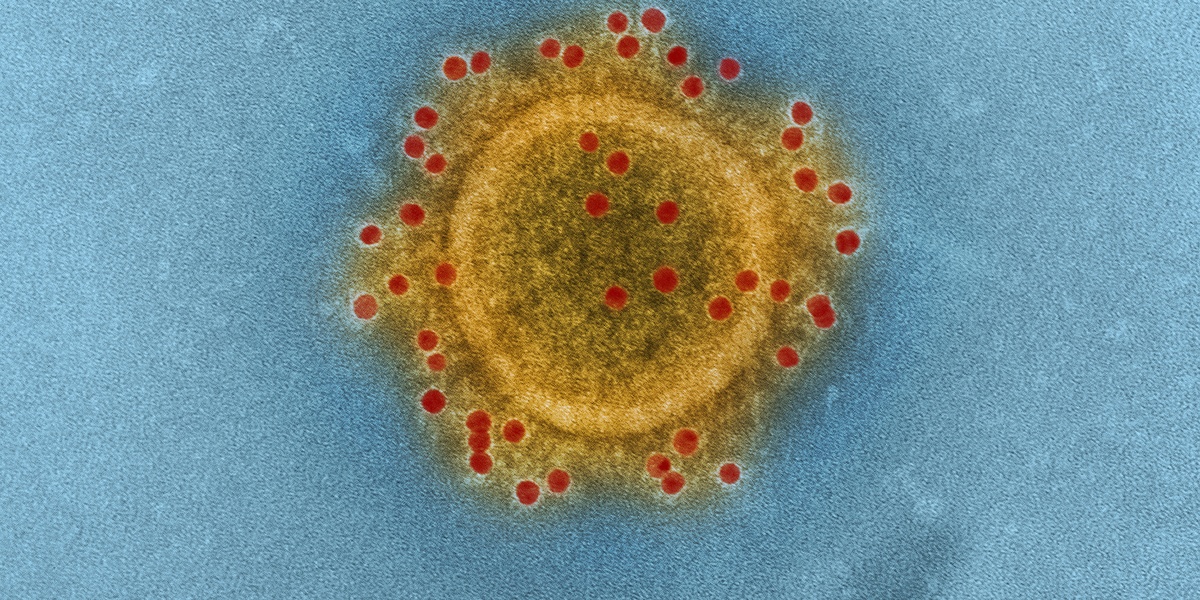

COVID-19

COVID-19 is caused by SARS-CoV-2, commonly producing fever, cough, fatigue and loss of smell; severe cases cause pneumonia and long-term symptoms. Global since 2019; spreads by respiratory routes. Vaccines and masks reduce risk; treatments and antivirals available for high-risk patients.